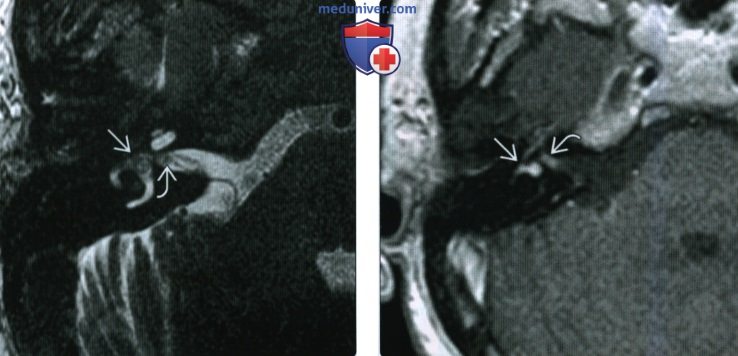

КТ анатомия сосцевидного отростка: особенности и показания